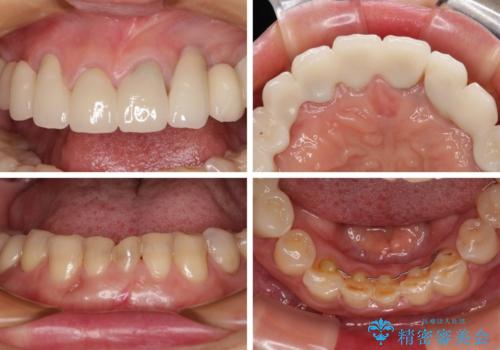

- 割れていると言われて放置してしまった歯や、前歯のデコボコなどが気になるとのことで来院された患者様です。

左上の歯は割れてしまっており、抜歯のうえインプラント治療が必要であり、他にも抜歯の必要な歯がある状態でした。

上顎はほぼ全ての歯をセラミッククラウンにて補綴治療を行う必要があるため、気になるデコボコや深い咬み合わせを改善するために下顎と上顎の臼歯部の矯正治療を行うこととしました。

並行して左下にはインプラントを埋入し、矯正治療を終えると同時に補綴治療を行うこととしました。

過蓋咬合(下顎前歯が隠れてしまうほどの深い咬み合わせ)のため、スムーズに歯が動かず矯正治療に時間がかかりましたが、無事に仕上げることができました。